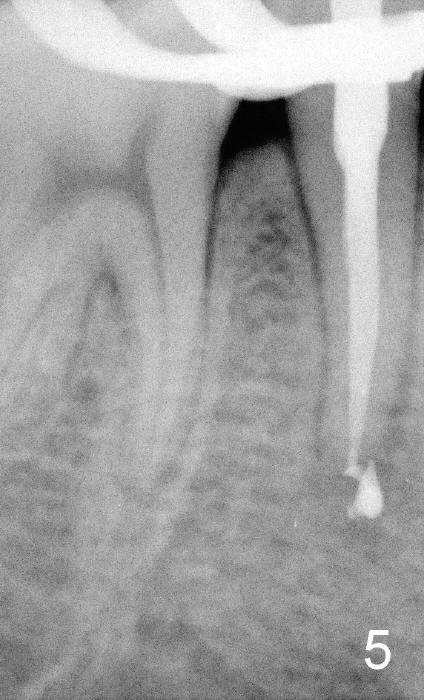

上集发表时,还没有见到病人,这集回答卢红医师疑问(下面)。今天病人来诊所诊治,他没有任何症状,右下五号牙根尖瘘道(图一箭头)是以前牙齿矫正医生发现的,咬合面中央隆起(图二箭头),后者中心好像有个小开口。对侧仿佛没有同样病变(图三*:左下五)。按照方柄忠大夫建议,根管治疗前做活力测试(Endo Ice):右下五的确死髓,有轻度扣痛。